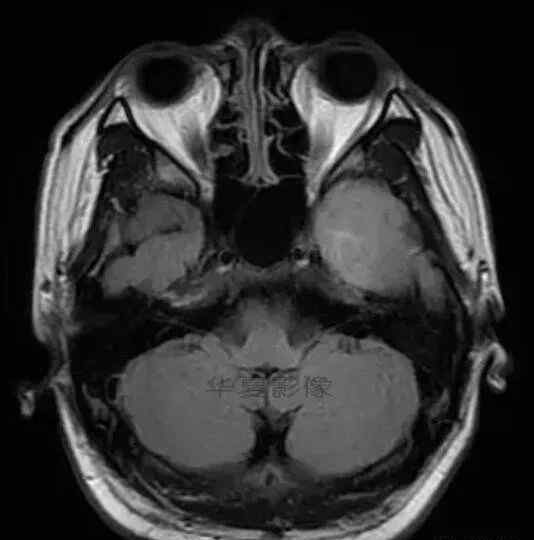

1.左侧颞叶、海马和岛叶T1WI信号低,T2WI信号高

2.病变没有明显的边界

3.占用效果不明显

4.豆状核不受影响